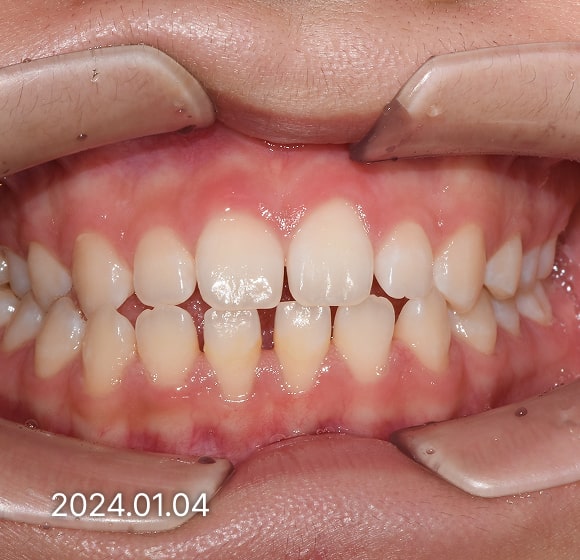

BEFORE / AFTER

전후 변화로 보는 치료사례

본 사진은 진심을담은치과교정과 치과의원에서

치료한 환자의 동일 인물 전·후 사진입니다.

개인의 구강 상태 및 관리 방법에 따라 통증 및 잇몸 염증,

턱관절 불편감 등의 부작용이 발생할 수 있습니다.

치료 전 치료 후

덧니, 삐뚤한 치열

돌출입

반대교합(비수술)

성장기 교정

과개교합

개방교합

치열공간, 벌어진 앞니

매복치아

악교정 수술 교정

결손치

부분교정

인비절라인